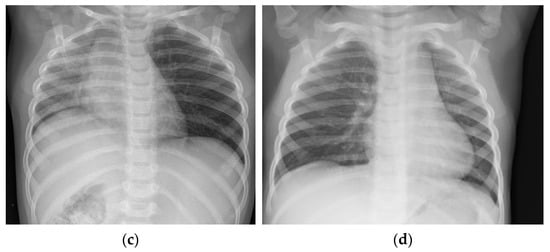

In the analyzed group, X-ray imaging results included: evidence of foreign body (metal objects), unilateral pneumothorax or atelectasis, intensified vascular pattern, emphysema, and mediastinum dislocation (Figure 3).

Figure 3.

X-ray imaging results. (a) Evidence of foreign body in right bronchi; (b) intensified vascular pattern; (c) mediastinum dislocation to right side; (d) mediastinum dislocation to left side.

When physical examination reveals dyspnea, cough, and excessive respiratory effort or fever, and chest X-ray image presumes a plausible foreign body aspiration, even if no choking episode was observed, it is recommended that rigid bronchoscopy be performed. Oversight and foreign body retention in lower airways may lead to serious adverse results [,]. Chest X-ray may show obvious evidence of foreign body (metal objects), but most times, radiologic image indirectly suggests the presence of an obstacle in the lower airways; in these cases, unilateral pneumothorax or atelectasis, emphysema, and mediastinum dislocation could be observed [,].